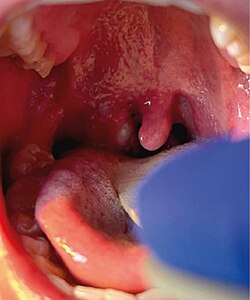

Right tonsillar enlargement with an overlying pustular lesion during the outbreak.

Unusually, none of these new cases had any known contact history with the previous three confirmed cases, which suggested a kind of transmission that had not been seen before,[63] a wider community transmission of the virus in the London area. The UKHSA stated that the risk to the general public remained "very low".[62][64] Patients with active monkeypox infection were confirmed to be hospitalised at the Royal Victoria Infirmary in Newcastle upon Tyne and at the Royal Free Hospital and Guy's Hospital in London.[62]